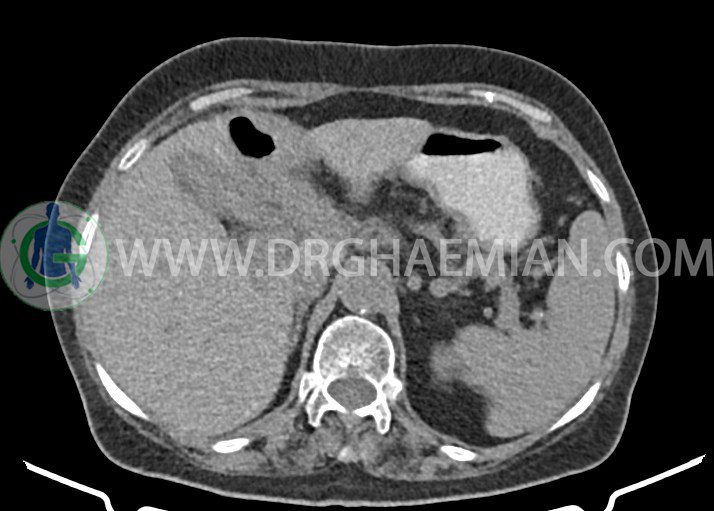

سی تی اسکن شکم یکی از روش های تصویربرداری با سی تی اسکن است. این روش با استفاده از اشعات ایکس تصاویر عرضی از ناحیه شکمی ایجاد میکند. در این کیس چندین سنگ کیسه صفرا، افزایش ضخامت دیواره کیسه صفرا، لنفادنوپاتی و کلسیفیکاسیون دیواره آئورت دیده می شود.

در سی تی اسکن اسپیرال شکم و لگن با و بدون کنتراست خوراکی و وریدی – پروتکل تری فازیک (مولتی دیدکتور 16 با مقاطع ظریف و بازسازی های ساژیتال و کرونال) :

تصویر سنگ های متعد به قطر تا 6mm در کیسه صفرا

افزایش ضخامت دیواره کیسه صفرا به ویژه در ناحیه فوندوس همراه با fat stranding در اطراف آن و چند لنفادنوپاتی به حداکثر SAD= 15mm در لیگامان گاستروکولیک و در مدیال کیسه صفرا

لنفادنوپاتی با حداکثر SAD= 14mm در ائورتوکاوال و پورتاهپاتیس ، بالاتر از عروق رنال

تصویر درن اوپک مجاور کولون صعودی و خم کبدی کولون

tract درن قبلی همراه با fat stranding در اطراف آن ، بین خم کبدی کولون و کیسه صفرا

توده های سالید به قطر 12mm و 13mm در چربی پاراکاردیاک راست و به قطر 12mm در اومنتوم مجاور طحال

کلسیفیکاسیون دیواره آئورت